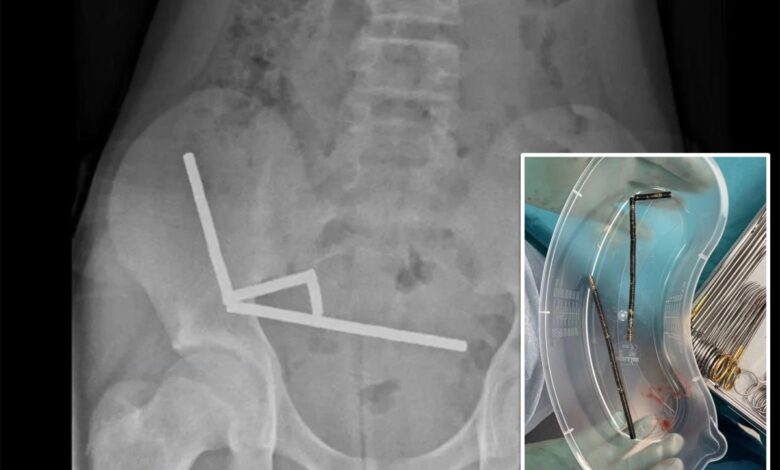

Rentgen odhalil čtyři řetězy magnetů uložené v různých částech jeho střev, stahují se a přerušují průtok krve do blízké tkáně.

13letému novozélandskému chlapci byla odstraněna část střev poté, co spolkl více než 100 vysoce výkonných magnetů. New Zealand Medical Journal

Lékaři uvedli, že tlak způsobil četné skvrny nekrózy – oblasti odumřelé střevní výstelky – vyžadující nouzovou operaci.

Lékaři uvedli, že každý z magnetů měří 5 x 2 milimetry a uvnitř chlapcových střev se shlukly do čtyř rovných linií. Magnetický tah způsobil, že části střeva k sobě přilnuly a účinně sevřely tkáň mezi nimi.